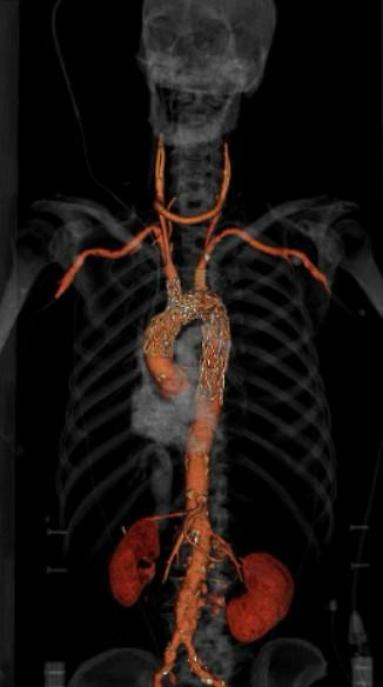

BARI - Un intervento mai eseguito prima in Puglia ha segnato una nuova frontiera per la cardiochirurgia vascolare. Al Policlinico di Bari è stata portata a termine con successo la prima sostituzione completa dell’arco aortico mediante procedura endovascolare, una tecnica mini-invasiva che ha permesso a un paziente di 80 anni di superare una diagnosi considerata senza alternative.

Nel nuovo approccio endovascolare, invece, l’accesso avviene attraverso piccole incisioni all’inguine, da cui vengono inseriti cateteri e protesi guidati da imaging radiologico di precisione. “Questa modalità – spiega Angiletta – riduce drasticamente i rischi operatori, i tempi di anestesia e di degenza, garantendo una ripresa più rapida, soprattutto nei pazienti anziani o con altre patologie”.

L’intervento è stato reso possibile grazie alle piattaforme di imaging e ai sistemi di navigazione di ultima generazione di cui il Policlinico è dotato, capaci di assicurare massima precisione anche nei distretti anatomici più complessi.